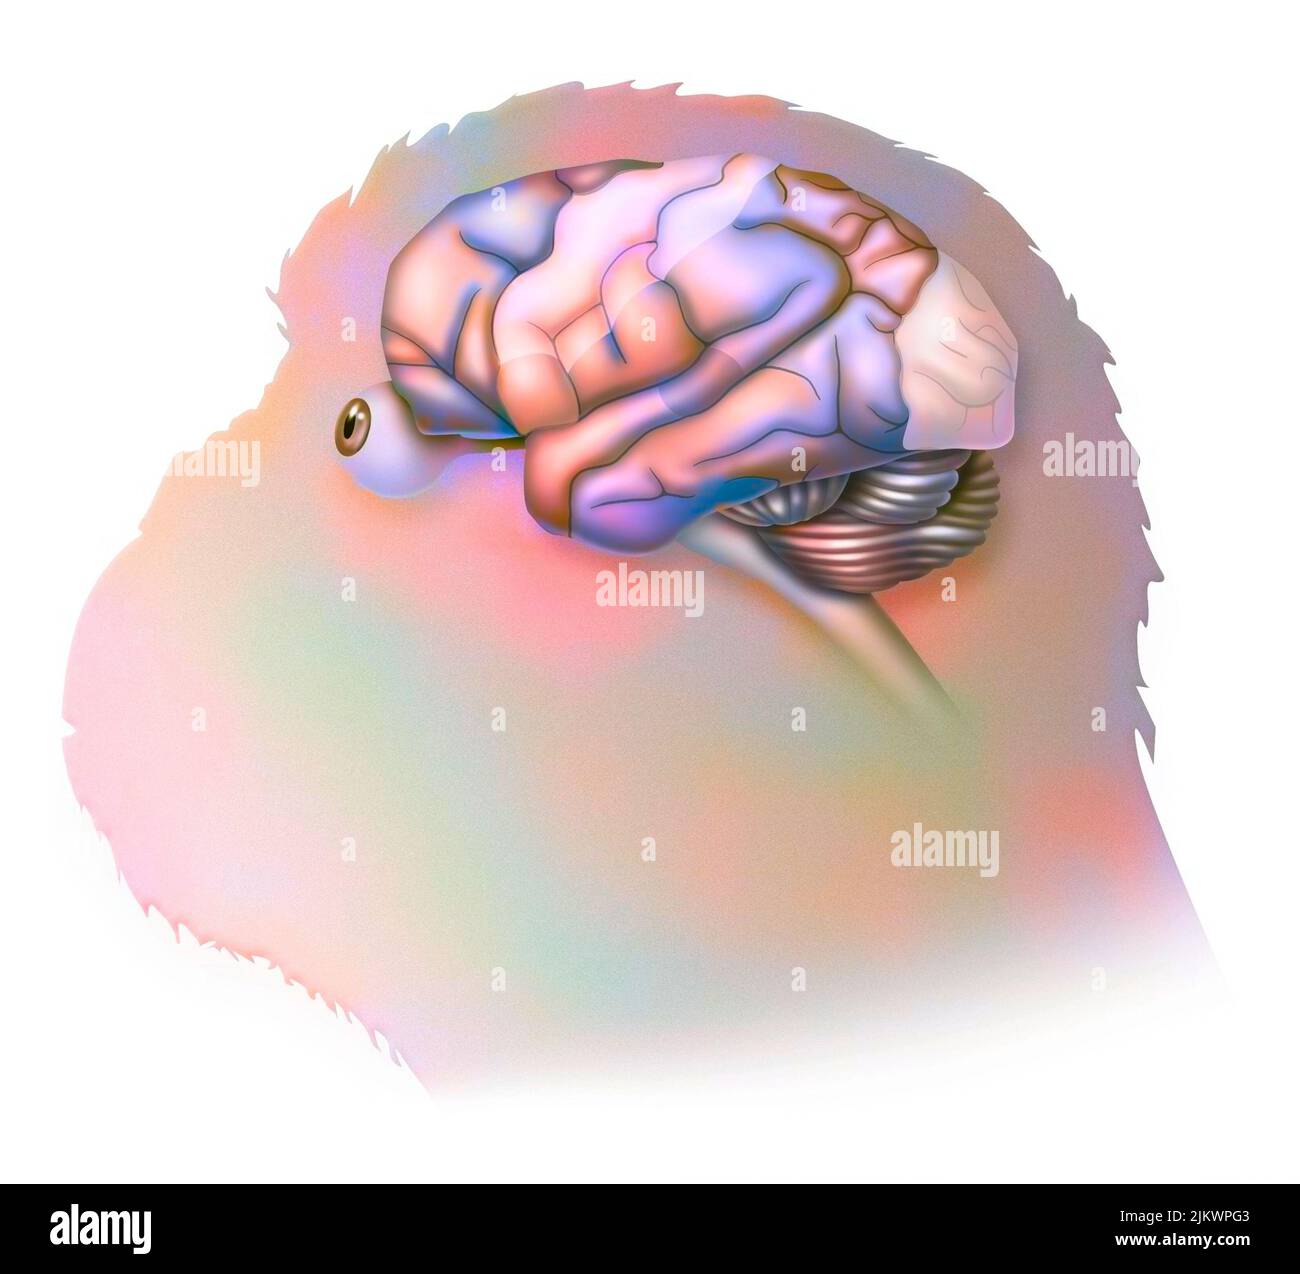

RF2JKWPG7–Troisième étape dans la façon dont le cerveau fonctionne quand vous tombez amoureux: La prise de décision.

RF2JKWPG3–Cerveau dans le chimpanzé avec ses zones (cognitives, auditives, visuelles) et cortex (moteurs, sensoriels).